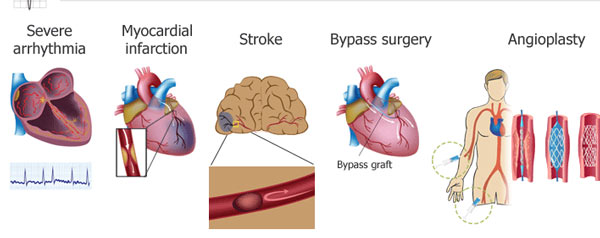

আর সিঙ্গল বা ডাব্ল চেম্বার পেসমেকার বসাতে হবে না? করাতে হবে না অ্যাঞ্জিওপ্ল্যাস্টি? প্রয়োজন কি অনেকটাই কমে যাবে সুজটিল কার্ডিও-থোরাসিক সার্জারিরও?

আর সিঙ্গল বা ডাব্ল চেম্বার পেসমেকার বসাতে হবে না? করাতে হবে না অ্যাঞ্জিওপ্ল্যাস্টি? প্রয়োজন কি অনেকটাই কমে যাবে সুজটিল কার্ডিও-থোরাসিক সার্জারিরও?

ওই ‘রিজেনারেশন’ পদ্ধতিতে আমাদের মতো স্তন্যপায়ীদের হার্ট এক দিন শরীরের ভেতরেই পুরনো নষ্ট হয়ে বা পচন ধরে যাওয়া কোষ, কলাগুলিকে ‘বাতিল’ করে দিয়ে তাদের জায়গায় নতুন নতুন কোষ, কলাগুলিকে একেবারে স্বাভাবিক নিয়মেই গায়ে-গতরে বাড়িয়ে তুলতে পারবে। একেবারে স্বাভাবিক নিয়মেই সেই কোষ, কলাগুলিকে হার্টে ছড়িয়ে দিতে পারবে। তাদের সুস্থ, সবল রাখার জন্য যা যা করণীয়, সেই সব কিছুই করতে পারবে। নিজেকে বাঁচিয়ে রাখা, সচল, সবল, সুস্থ রাখার জন্য হার্ট যদি প্রয়োজনীয় কাজগুলি আপনাআপনিই করে ফেলতে পারে, তা হলে আর তাকে ঠিকঠাক ভাবে চালিয়ে নিয়ে যাওয়ার জন্য বাইরে থেকে পেসমেকার বসাতে হবে কেন? কেনই-বা অ্যাঞ্জিওপ্ল্যাস্টির মতো হার্টে করতে হবে হরেক রকমের সুজটিল অস্ত্রোপচার? কেনই-বা প্রয়োজন হবে কার্ডিও-থোরাসিক সার্জারির?